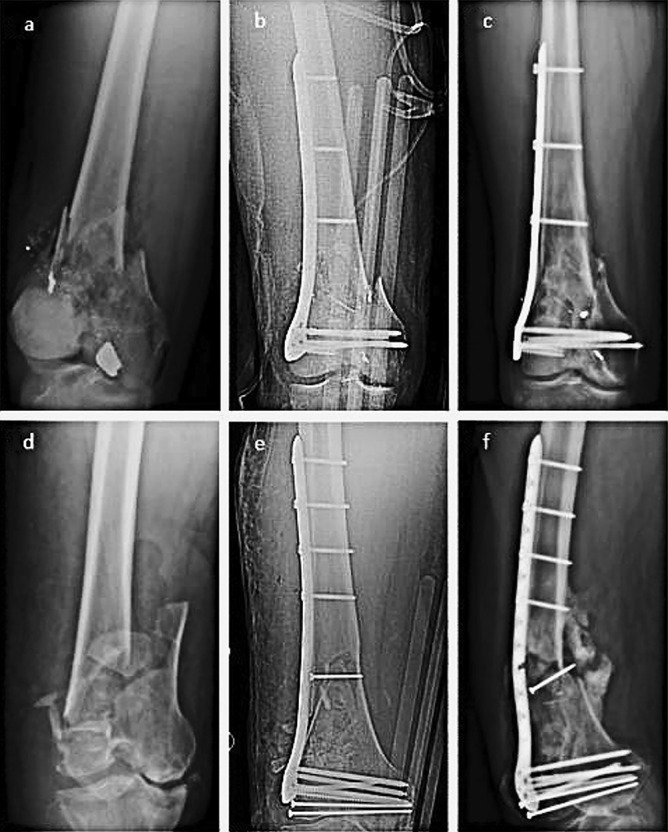

Objectives: Multiple treatment modalities exist for treating distal femur fractures. Lateral locked plating has become the method of choice because it prevents loss of reduction due to varus collapse, but has been associated with nonunion rates of up to 30%. Titanium implants may provide a more optimal biomechanical environment for fracture healing. The primary aim of this study is to evaluate nonunion rates and risk factors for nonunion in a series of distal femur fractures stabilized with modern locked titanium implants using all nonlocking diaphyseal fixation. A secondary aim is to evaluate whether diaphyseal fixation with nonlocking screws is associated with fixation complications.

Results: Eighty-one fractures met inclusion criteria with 16 fractures resulting in nonunion (19.75%). Comparing union and nonunion cohorts, nonunions were found to be associated with higher body mass index (P = 0.001). Fixation construct data found nonunions had a higher average number of diaphyseal screws (4.25 vs. 3.74, P = 0.038). Subgroup analysis found a nonunion rate of 4.2% (1 out of 24) in fractures with 3 diaphyseal screw fixation versus 26.3% (15 out of 57) with 4 or more diaphyseal screws (P = 0.038). No diaphyseal fixation failures were noted with nonlocking diaphyseal screw fixation.

Conclusion: Our study found using a titanium construct produced a nonunion rate of 19.75%, comparable with historic rates. Interestingly, diaphyseal fixation with more than 3 screws led to higher nonunion rates. No catastrophic failures were observed involving the diaphyseal nonlocking screw fixation.